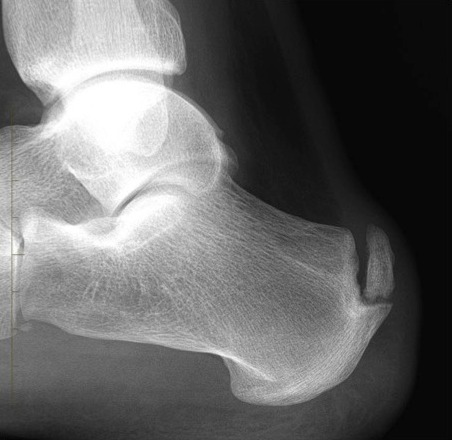

The symptoms of this condition are distinct enough that advanced imaging techniques are rarely required for a diagnosis. However standing X-rays of the foot are useful in determining the presence of a heel bump or 'Haglund's deformity' or calcification within the insertion of the tendon, both of which are surgical targets in the treatment of the disease.